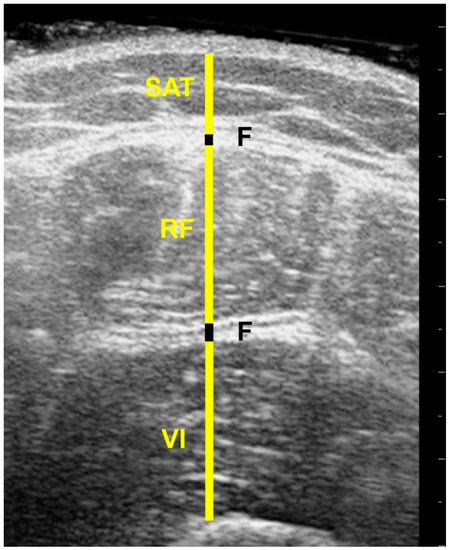

2.3. US Imaging Acquisition

2.5. Image Processing

- Mechelli, F.; Arendt-Nielsen, L.; Stokes, M.; Agyapong-Badu, S. Inter-rater and intra-rater reliability of ultrasound imaging for measuring quadriceps muscle and non-contractile tissue thickness of the anterior thigh. Biomed. Phys. Eng. Express 2019, 5, 037002. [Google Scholar]

- Delaney, S.; Worsley, P.; Warner, M.; Taylor, M.; Stokes, M. Assessing contractile ability of the quadriceps muscle using ultrasound imaging. Muscle Nerve 2010, 42, 530–538. [Google Scholar] [CrossRef] [PubMed]

- Agyapong-Badu, S.; Warner, M.; Samuel, D.; Narici, M.; Cooper, C.; Stokes, M. Anterior thigh composition measured using ultrasound imaging to quantify relative thickness of muscle and non-contractile tissue: A potential biomarker for musculoskeletal health. Physiol. Meas. 2014, 35, 2165–2176. [Google Scholar] [CrossRef]